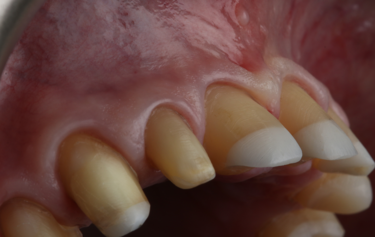

Figure 2: Frontal retracted view – before

This 58-year old female patient presented showing advanced tooth surface loss and loss of occlusal-vertical dimension (OVD) with passive overeruption of her anterior segment. She was struggling to enjoy the foods she loved and over the last few years had recoiled herself from any form of social engagement as she found public eating very difficult. She was very embarrassed of her smile and only smiled with her mouth closed. She had been in a profession with a lot of stress and had suffered in the past with gastric reflux. She also admitted to drinking 2 cans of carbonated soft drink every day for over 30 years.

Her main concern was the size discrepancies and tooth wear that was obvious within her smile. She had a low lip line and slightly deficient buccal corridors (Fig. 1). She was posturing into a pseudo-class 3 occlusion with passive overeruption of all her teeth, more noticeable on the anterior upper and lower labial segment (Fig. 2). She had missing posterior teeth and so all her mastication was on a reduced dental arch.

Her teeth showed tooth surface loss and passive eruption of the both the upper and lower anterior segment with excessive upper gum on show during forced wide smiling. The diagnosis of severe attrition and tooth surface loss was made, as a result of previous acidic reflux, stress-related parafunction, and a highly acidic diet, which lead to the erosion and subsequent collapse of the arches and loss of occlusal-vertical dimension.